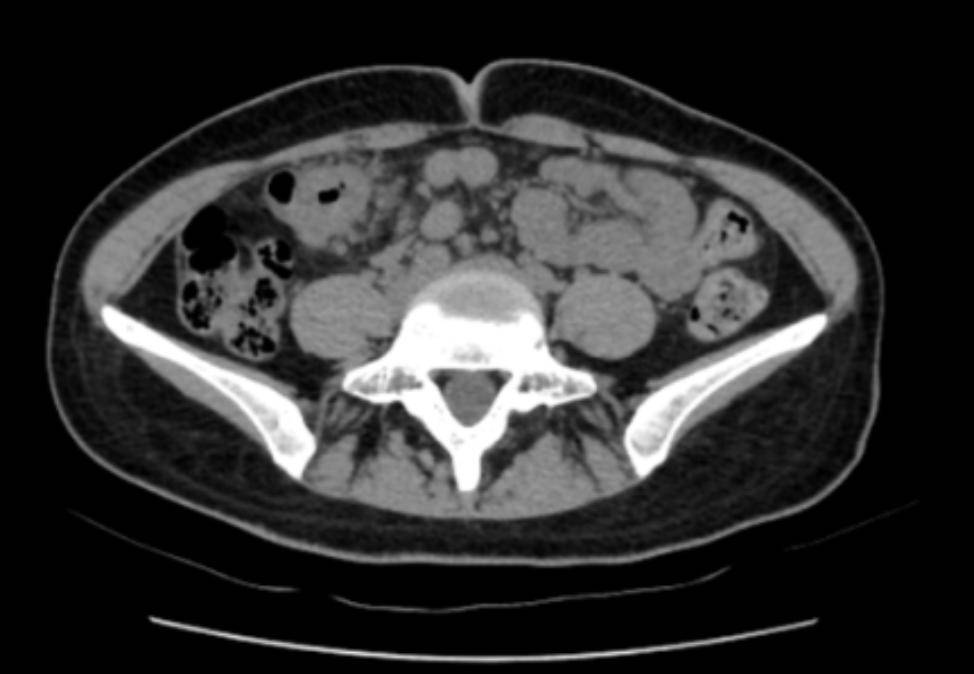

“脐周疼痛对应的多是小肠问题,右上腹的包块却指向肝胆、结肠等器官,这两者对不上。”医生立刻警觉起来,当即安排王女士做腹部CT检查。影像结果很快出来:结肠近肝曲处肠壁可疑增厚,肠腔狭窄——这个信号让诊疗团队的神经瞬间紧绷。

三天后,消化内镜中心孙舒仰医生操作的结肠镜顺利进行。当镜头探至升结肠近肝曲——正是之前查体摸到包块的位置时,一个不规则肿物赫然出现: 它环绕肠腔2/3,表面糜烂溃疡还附着污苔,质地脆弱一碰就出血,肠壁已变得僵硬,管腔也出现偏心性狭窄,万幸肠镜还能勉强通过。“高度怀疑结肠癌。”孙舒仰医生当场判断。